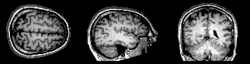

Tomografia rezonansu magnetycznego (MRI)

Obecnie wykorzystanie rezonansu magnetycznego jest coraz powszechniejsze w praktyce klinicznej. W ostatnim dziesięcioleciu jakość obrazu otrzymywanego w czasie badania uległa znaczącej poprawie, dzięki czemu rezonans magnetyczny stał się doskonałym uzupełnieniem diagnostyki w wielu dziedzinach medycyny. Zastosowania MRI stały się metodą z wyboru w nieinwazyjnej diagnostyce obrazowej nie tylko serca[6].